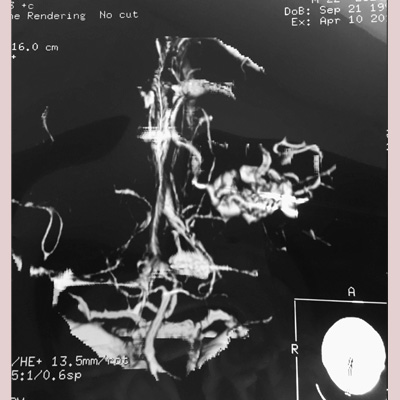

Brain Arteriovenous Malformations (AVM), as well as other Vascular Malformations are resected with sophisticated Microsurgical techniques in appropriately selected cases, or referred for Endovascular Embolization, Stereotactic Radiosurgery (SRS), or a combination of these treatment modalities with high success rates and safety and efficacy.